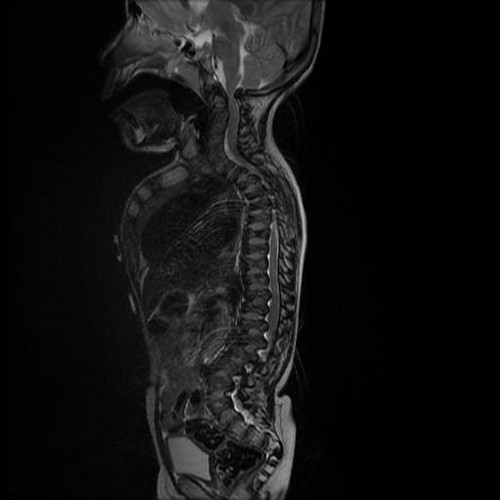

Рентгеновские снимки крестцово-копчикового отдела позвоночника